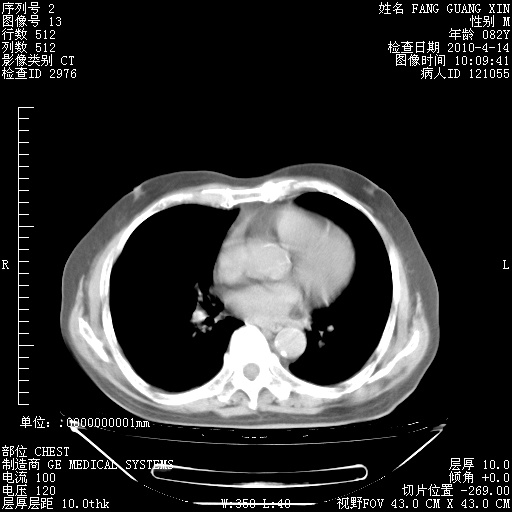

4月14日肺部CT

23.JPG

24.JPG

25.JPG

26.JPG